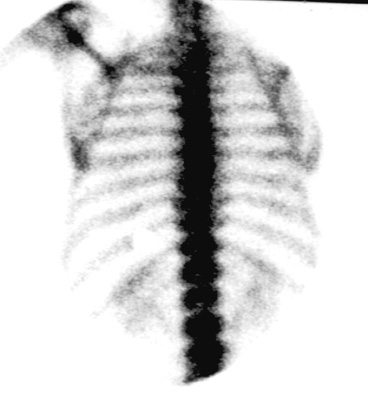

This is a 68 y/0 man with prostate

carcinoma and a PSA of 127.

Radionuclide bone imaging is the best method to survey the skeleton for evidence of metastatic spread of tumors which frequently go to bone. These tumors include breast carcinoma in women and prostate carcinoma in men. Other tumors which frequently go to bone include lung carcinoma, renal carcinoma and GI maligancies.